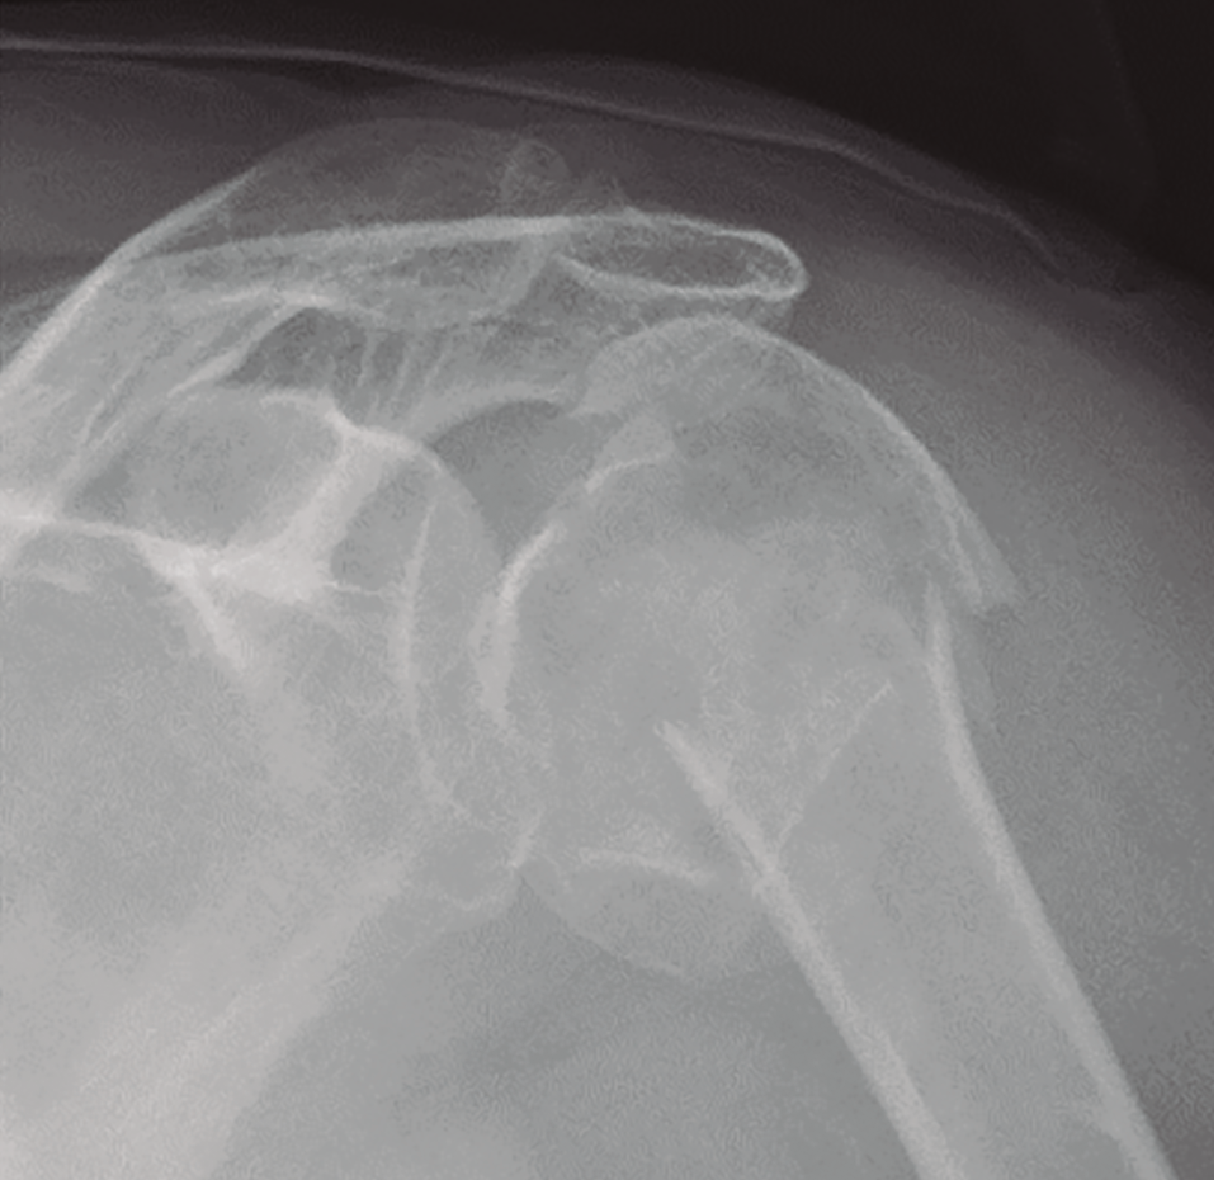

Shekelle et al.(9) concluyen que no existe evidencia en cuanto a la elección del tipo de tratamiento, pero sí resulta de gran importancia individualizar el tratamiento valorando de forma integral al paciente, considerando el grado de desplazamiento, la densidad ósea, la edad y las lesiones asociadas (Figura 5).

Figura 5. Radiografía simple de fractura del húmero proximal.